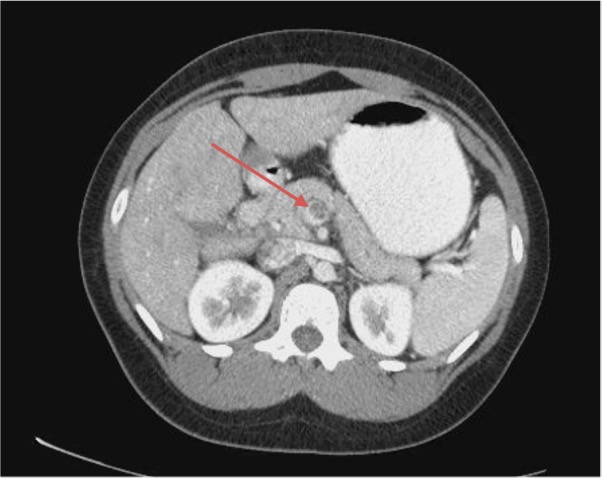

The patient had persistent pain upon reexamination, so a computed tomography (CT) scan of the abdomen and pelvis with oral and intravenous contrasts was conducted. Results revealed a thrombosed superior mesenteric vein and peripheral branches with retroperitoneal fat stranding about the vessel, which was compatible with thrombophlebitis (Figures 1 and 2). The transverse descending and proximal sigmoid colons were also mildly thickened, which was suspected to be more related to underdistention.

The CT findings may reveal central lucency in the mesenteric vein, enlargement of the superior mesenteric vein, a sharply defined vein wall with a rim of increased density, as well as intestinal edema.5 Intramural gas typical of bowel gangrene has also been described.12